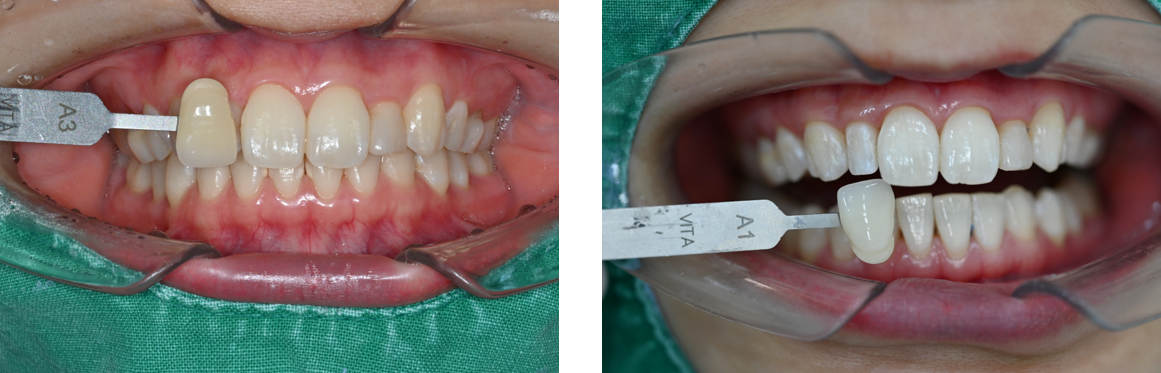

스케일링 받으러 갔다 미백 상담했는데 후기보고 믿음이 있던 터라 미백 진행해봤어요 당일에 바로 되고 친구들이 미백 받으면 이 시리다고 해서 쫄았는데 전 하나도 안시리던뎅.. 그리고 효과 진짜 좋아서 뽀얀 치아가 돼서 신기해용